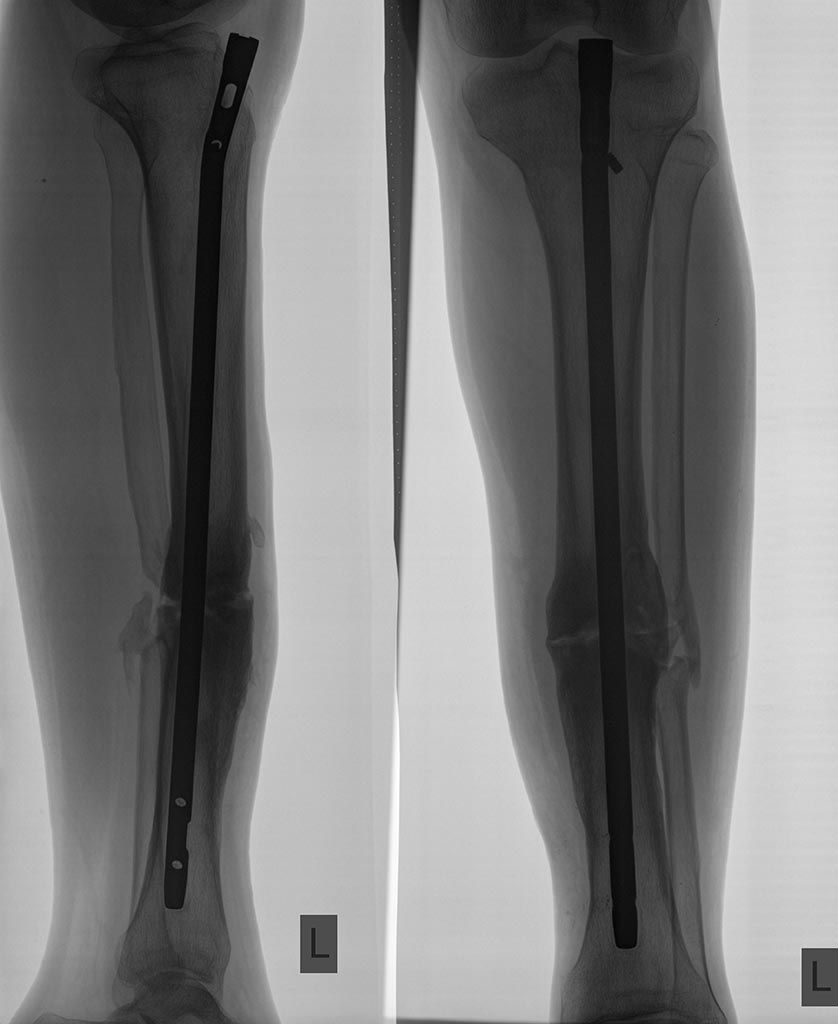

Пациент,19лет,травма в ДТП 1,5года назад ( ЧМТ,перелом бедра,перелом обеих костей голени). Проведен БИОС бедра и голени. Бедро срослось, стержень удален через год. Вопрос по голени: есть ли шанс на сращение, принимая во внимание возраст пациента(если ждать,то сколько) или делать реостеосинтез с рассверливанием сейчас? Клинически пациента ничего не беспокоит.

здравствуйте! По-моему все-таки надо выполнить реостеосинтез, попутно исправив вальгус и угол кзади. Технически никаких проблем с удалением старого стержня и установкой нового быть не должно.

мне кажется, рентгенологически говорить о несращении здесь нельзя (балки вроде как перекидываются, признаков резорбции вокруг стержня нет). Это подтверждает и полное отсутствие жалоб. Я бы подождал 3-4 мес и повторил снимки. Думаю смещением такого рода можно и пренебречь, хотя исходно стараемся такого не оставлять.Наверное, здесь есть и еще некоторые детали, к которым можно придраться, но в наст. время они не актуальны. Вероятнее всего имелась тенденция к образованию гипертрофич. Л.С., но молодость взяла свое и сращение все же наступило.

Очень мало информации - на каком бедре был перелом, была ли иммобилизация, когда началась нагрузка и была выполнена динамизация стержня на голени, судя по сломанному винту, очевидно, динамизация была выполнена несвоевременно, и какая ЧМТ - была ли или есть неврология? Если нет неврологии, контрактур надо дать полную нагрузку - рентгенконтроль через 3 месяца. "Ничего не беспокоит" - при каком двигательном режиме?l

Перелом бедра-на противоположной стороне.Иммобилизации не было, Нагрузка через 10-12 дней."Самодинамизация" произошла через 3мес. (остатки винтов удалены через год при удалении с бедра). ЧМТ-сотрясение,без последствий.Контрактур нет,нагрузка полная.

>Клинически пациента ничего не беспокоит.

Что, даже при опоре на колено торчащий стержень не чувствует? Повезло.

Если клинически значимой деформации нет, нога полностью, действительно полностью безболезненна

и опороспособна (нет хромоты, свободно бегает) - рентгенограмму лечить не надо. Можно наблюдать дальше, делая снимки раз в 6-12 мес.

Большое спасибо за ответ! "Торчащий" стержень чувствовал 6 мес. после операции. Клинически значимой деформации нет, нога действительно безболезненна и опороспособна (нет хромоты, свободно бегает и играет в футбол).